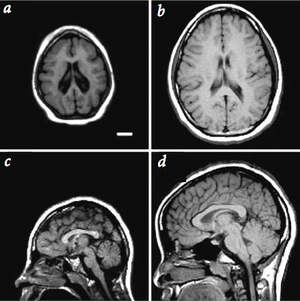

صورة أشعة تقارن بين الحالة القياسية و ميكروسيفالي